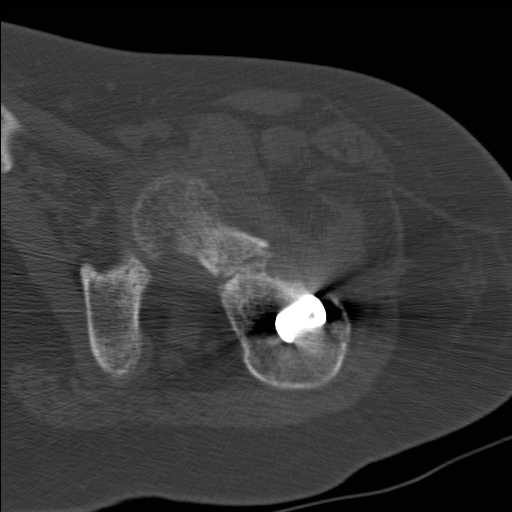

Перелом шейки бедра у девушки 19 лет. Чем лучше помочь?

Добрый день уважаемые коллеги. Во такая ситуация. Девушка 19 лет травму

получила в мае 2016г( изолированная травма, трансцервикальный перелом

шейки левого бедра). Соматически здорова. Лечилась по месту жительства

скелетным вытяжением в течении 1 месяца. Затем переведена в наше

учреждение. 18 июня выполнена операция, детали где , кто и как уточнять

не имеет смысла( из протокола операции: выполнялась передняя артротомия,

репозиция под визуальным контролем) . Учитывая характер выполненного

остеосинтеза, после операции постельный режим 6 недель. Снимки в

хронологии все выкладываю. КТ контроль сделан 2.09.16.  для оценки

состояния  головки бедра. Помогите, определиться с дальнейшей тактикой.